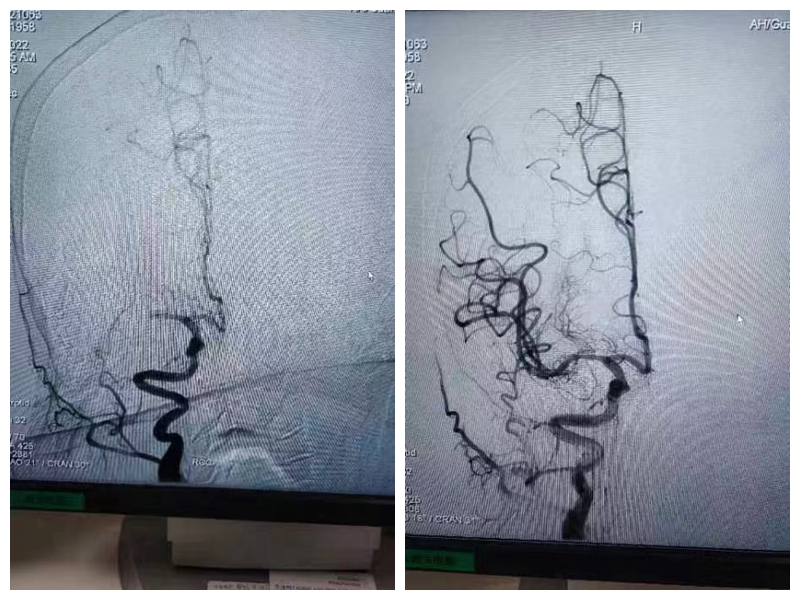

12月21日上午10:16分,一名突发脑梗死的患者被紧急送到广德市人民医院神经内科,卒中绿色通道团队立即接诊。患者左侧肢体完全瘫痪,NIHSS10分,患者新冠核酸显示阳性。冒着可能会被感染的风险,神经内科刘勇副主任毫不犹豫地给患者进行了急诊取栓手术。

下午13:30,在刘勇副主任和其他同事们的共同努力下,顺利完成手术,患者转危为安!症状好转,NIHSS3分,手术效果明显。